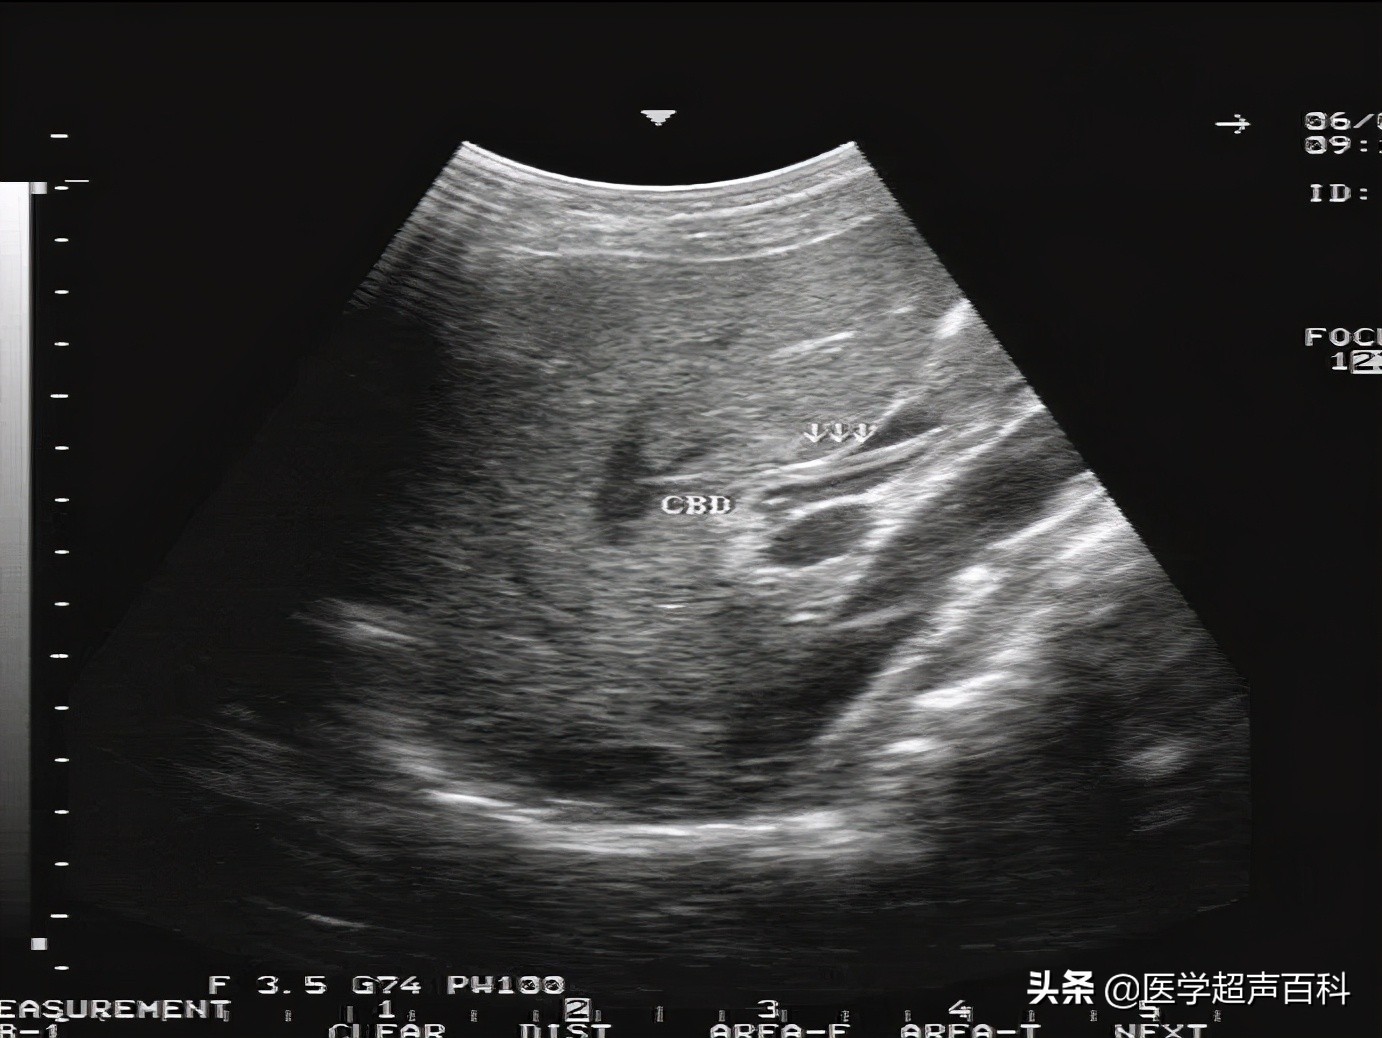

1.肝外胆管呈不同程度的扩张,胆总管常呈明显扩张。

2.扩张的胆管内有数毫米宽的平行双线状的高回声带,前端圆钝,形态自然、边缘清晰、光滑。光带间暗区是蛔虫的假体腔,其内可见间断的点线状高回声。蛔虫死后,其中心暗带逐渐变得模糊甚至消失。

4.实时超声探测看到虫体在胆管内蠕动是具有诊断意义的特异性表现。

超声显像诊断胆道蛔虫病是简便、实用而有效的方法,其准确率高达百分之九十五以上,如胆管扩张,胆汁充盈,可见到特征性双线状高回声带可作本病诊断的依据,如显示活蛔虫蠕动即可确诊。